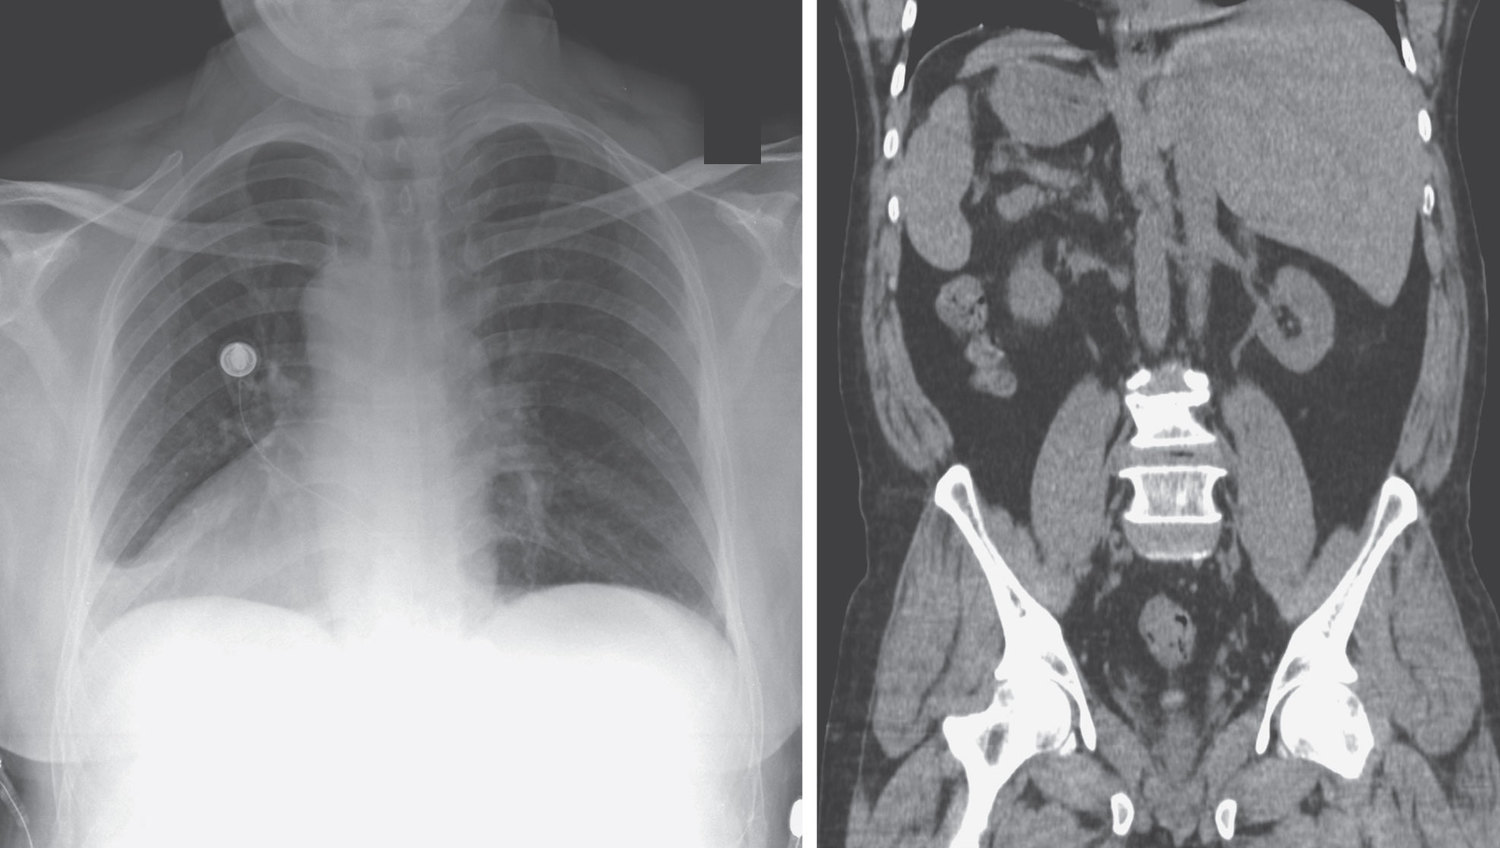

A 66-year-old man presented to the emergency department with a 3-day history of cough, congestion, and pain in his chest and on the left side of his abdomen. What is the abnormality noted incidentally on chest radiograph and computed tomography of the abdomen?

Situs inversus totalis